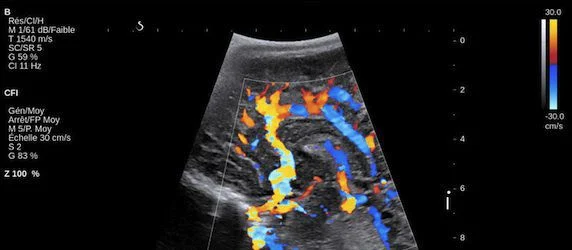

At the heart of healthcare’s most advanced ultrasound system is its UltraFast Imaging platform. This is currently the most sophisticated and speediest architecture on the market which acquires information 200 times faster than any other ultrasound system. The extreme velocity enables the company’s ShearWave Elastography scanning, the only real-time ultrasound imaging mode cleared by the FDA to measure and simultaneously display tissue stiffness in kilopascal, as well as UltraFast Doppler which speeds examination times and stands alone in its capabilities.

Aixplorer Expert Edition’s UltraFast Doppler is the most comprehensive Doppler available offering color frame rates up to 200 Hz and full spectral Doppler quantification, including peak velocity, instantaneously. This reduces the process of exams to seconds, with no need for compromise between frame rate and color box size, and saves time in everyday Doppler procedures making it ideal for renal transplants and pediatrics.